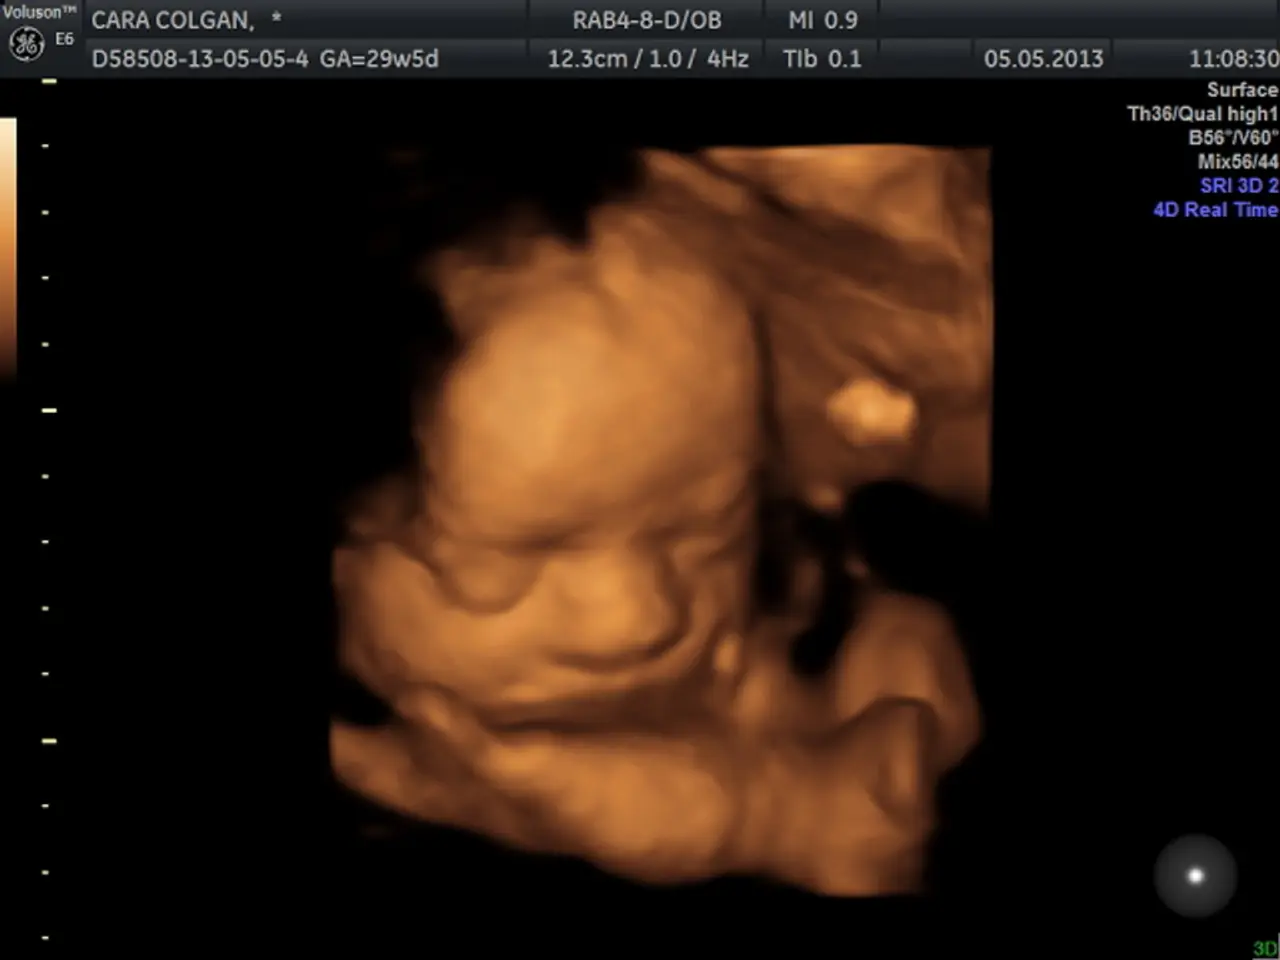

Fifteenth Yearly Examination of Fetal Echocardiography: Hearts that are Regular and Irregular

The course, designed and led by experts in the field, aims to provide a more in-depth understanding of fetal echocardiography. It covers essential topics such as fetal heart structure and function, potential abnormalities, and the latest advancements in the field. The course may even include practical sessions for hands-on learning and skill development.